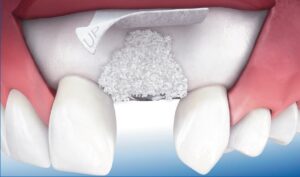

Для проведення імплантації необхідна наявність достатнього обсягу кісткової тканини. При її дефіциті буде потрібно проведення кісткової пластики. З цією метою може бути використана як власна кісткова тканина пацієнта (аутотрансплантат), так і донорський матеріал (аллотрансплантат), а також синтетичні матеріали (біокераміка, гідроксиапатит, фосфат кальцію) або ксенотрансплантати (на основі кісткової тканини тварин).

Для незнімного повного протезування зубів на імплантатах потрібно встановити від 6 до 8 імплантів – опор. При необхідності проводиться аугментація (нарощування) кісткової тканини ( синус – ліфтинг ) в окремих передбачуваних ділянках імплантації імплантів.

Це хірургічна операція по нарощуванню кісткової тканини в бічних відділах верхньої щелепи, для якісного встановлення імплантатів.

Як одна з методик автокісткової пластики, синус ліфтинг щелепи дозволяє відновити необхідний обсяг кісткової тканини альвеолярного відростка в передбачуваній області фіксації імплантату, за рахунок зменшення простору верхньощелепної (гайморової) пазухи.

Застосування остеопластики уможливлює відновлення втраченої кількості кісткової тканини, і тим самим, є підготовчим етапом перед імплантацією зубів.

При більшій пневматизації показаний закритий синус ліфтинг або м’який (soft) з доступом через канал ложа імплантату.

При наявному обсязі кісткової тканини менше 5 мм показаний відкритий синус ліфтинг – пластика дна верхньощелепної пазухи з доступом-перфорацією передньої стінки пазухи.

Суть цієї операції полягає в формуванні доступу через гребінь альвеолярного відростка в місці передбачуваного встановлення імплантату.

Через утворений отвір в каналі ложа імплантату, проводиться відшарування і підняття мембрани гайморової пазухи (мембрани Шнайдера).

Після підняття мембрани отриманий простір між дном гайморової пазухи і мембраною заповнюється остеотропним матеріалом.

Імплантат впроваджується в це, вже підготовлене ложе після введення матеріалу.

Методика підняття мембрани Шнайдера забезпечує установку і стабільність імплантату, за допомогою збільшення товщини нижньої стінки верхньощелепної пазухи.